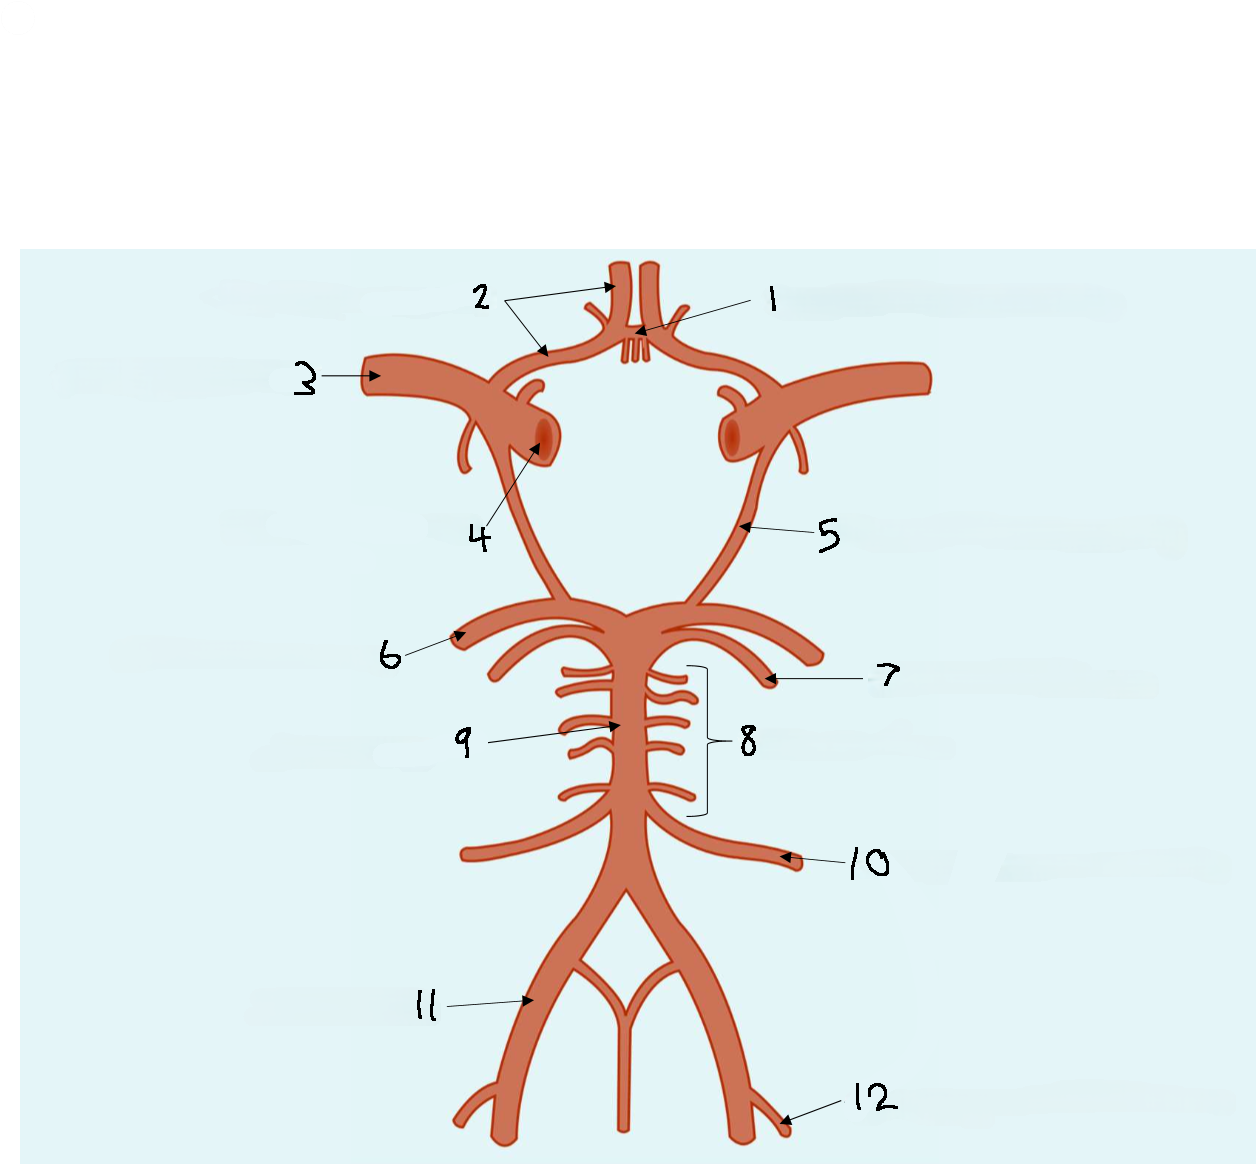

What is 1?

anterior communicating artery

What is 2?

anterior cerebral artery

What is 3?

middle cerebral artery

What is 4?

internal carotid artery

What is 5?

posterior communicating artery

What is 6?

posterior cerebral artery

What is 7?

superior cerebellar artery

What is 8?

pontine arteries

What is 9?

basilar artery

What is 10?

anterior inferior cerebellar artery

What is 11?

vertebral artery

What is 12?

posterior inferior cerebellar artery